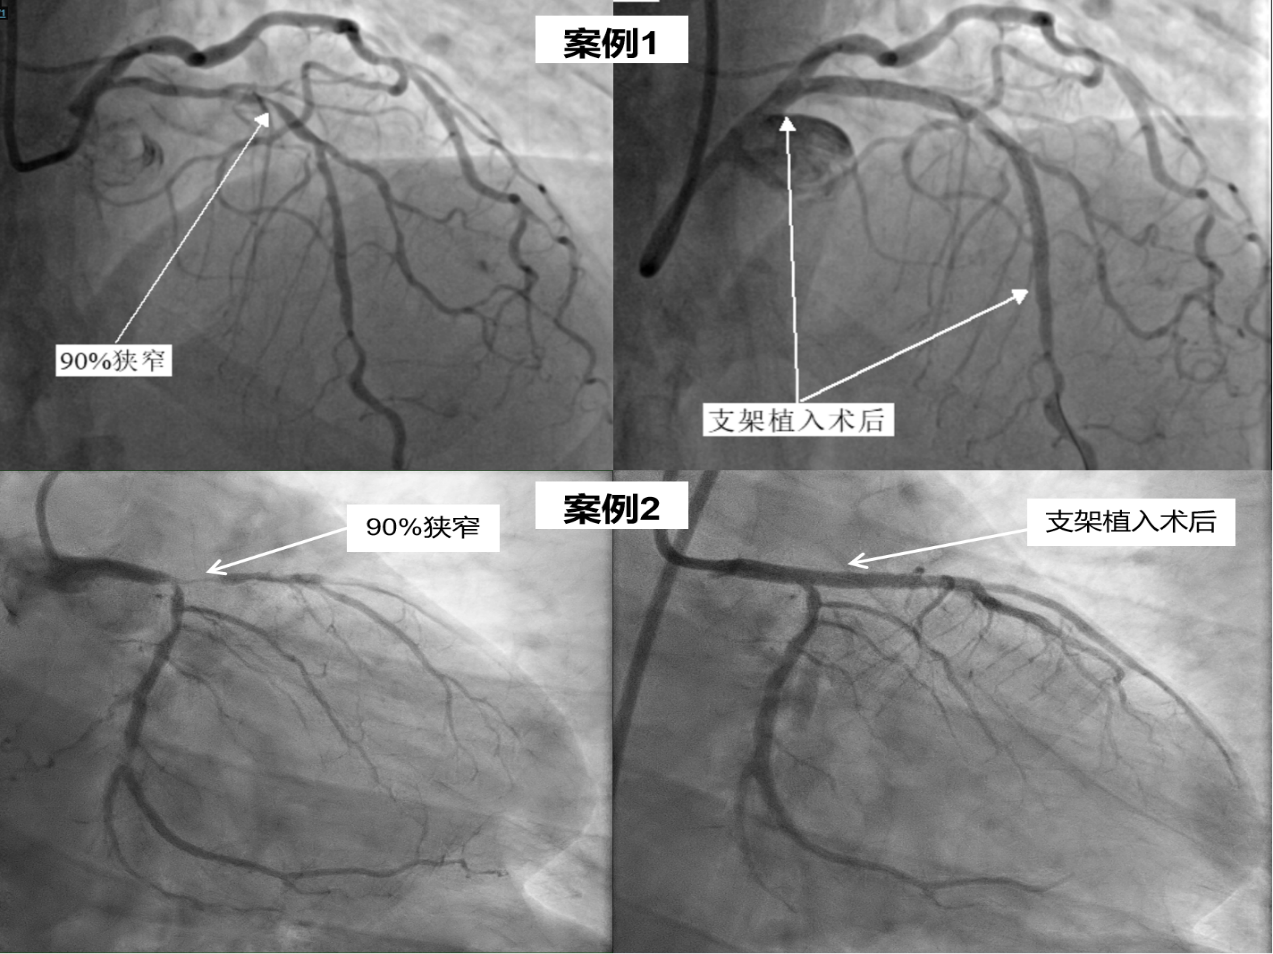

2025-07-24心血管堵了90%竟不自知!专科体检揪出“沉默”心梗 -